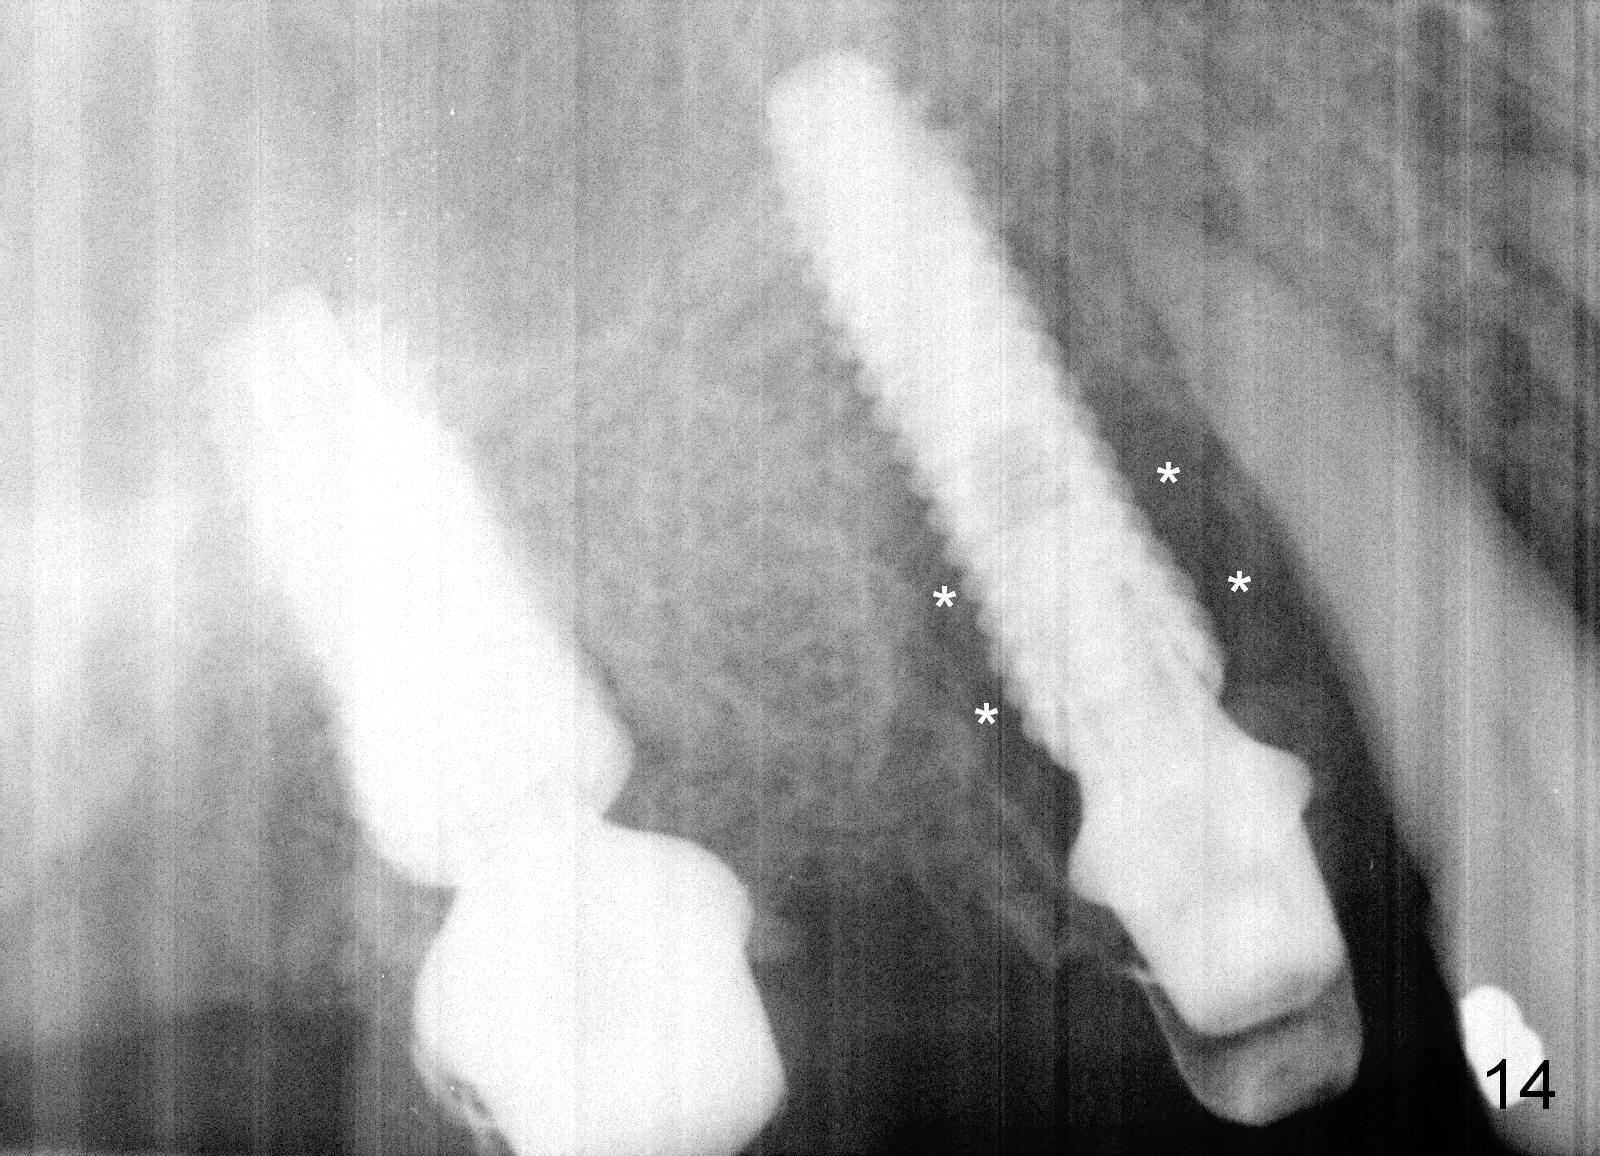

Two months and a half postop (#3,5 implantation), the patient agrees to have #6-8 to be extracted because of persistent infection. She reports dislodgement of the provisional at #3-5 using water pik. The provisional is found to be mobile. PA shows decrease in bone density around the implant at #5, probably due to proximity to the infection (Fig.14 *).